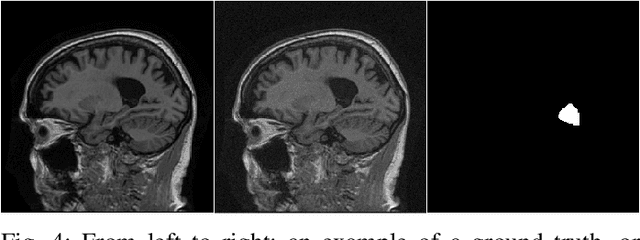

Abstract:In order to objectively assess new medical imaging technologies via computer-simulations, it is important to account for all sources of variability that contribute to image data. One important source of variability that can significantly limit observer performance is associated with the variability in the ensemble of objects to-be-imaged. This source of variability can be described by stochastic object models (SOMs), which are generative models that can be employed to sample from a distribution of to-be-virtually-imaged objects. It is generally desirable to establish SOMs from experimental imaging measurements acquired by use of a well-characterized imaging system, but this task has remained challenging. Deep generative neural networks, such as generative adversarial networks (GANs) hold potential for such tasks. To establish SOMs from imaging measurements, an AmbientGAN has been proposed that augments a GAN with a measurement operator. However, the original AmbientGAN could not immediately benefit from modern training procedures and GAN architectures, which limited its ability to be applied to realistically sized medical image data. To circumvent this, in this work, a modified AmbientGAN training strategy is proposed that is suitable for modern progressive or multi-resolution training approaches such as employed in the Progressive Growing of GANs and Style-based GANs. AmbientGANs established by use of the proposed training procedure are systematically validated in a controlled way by use of computer-simulated measurement data corresponding to a stylized imaging system. Finally, emulated single-coil experimental magnetic resonance imaging data are employed to demonstrate the methods under less stylized conditions.